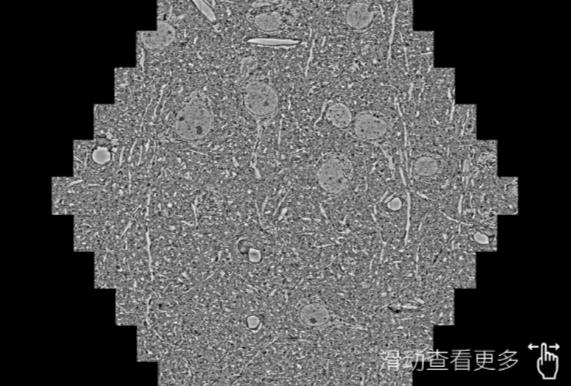

鼠脑切片。左图使用汕尾蔡司汕尾扫描电镜MultiSEM706对165μmx143pm面积区域成像,耗时仅需1.5秒。右图为鼠脑切片中30μm区域放大效果。样品由芝加哥大学B.Kasthuri提供。